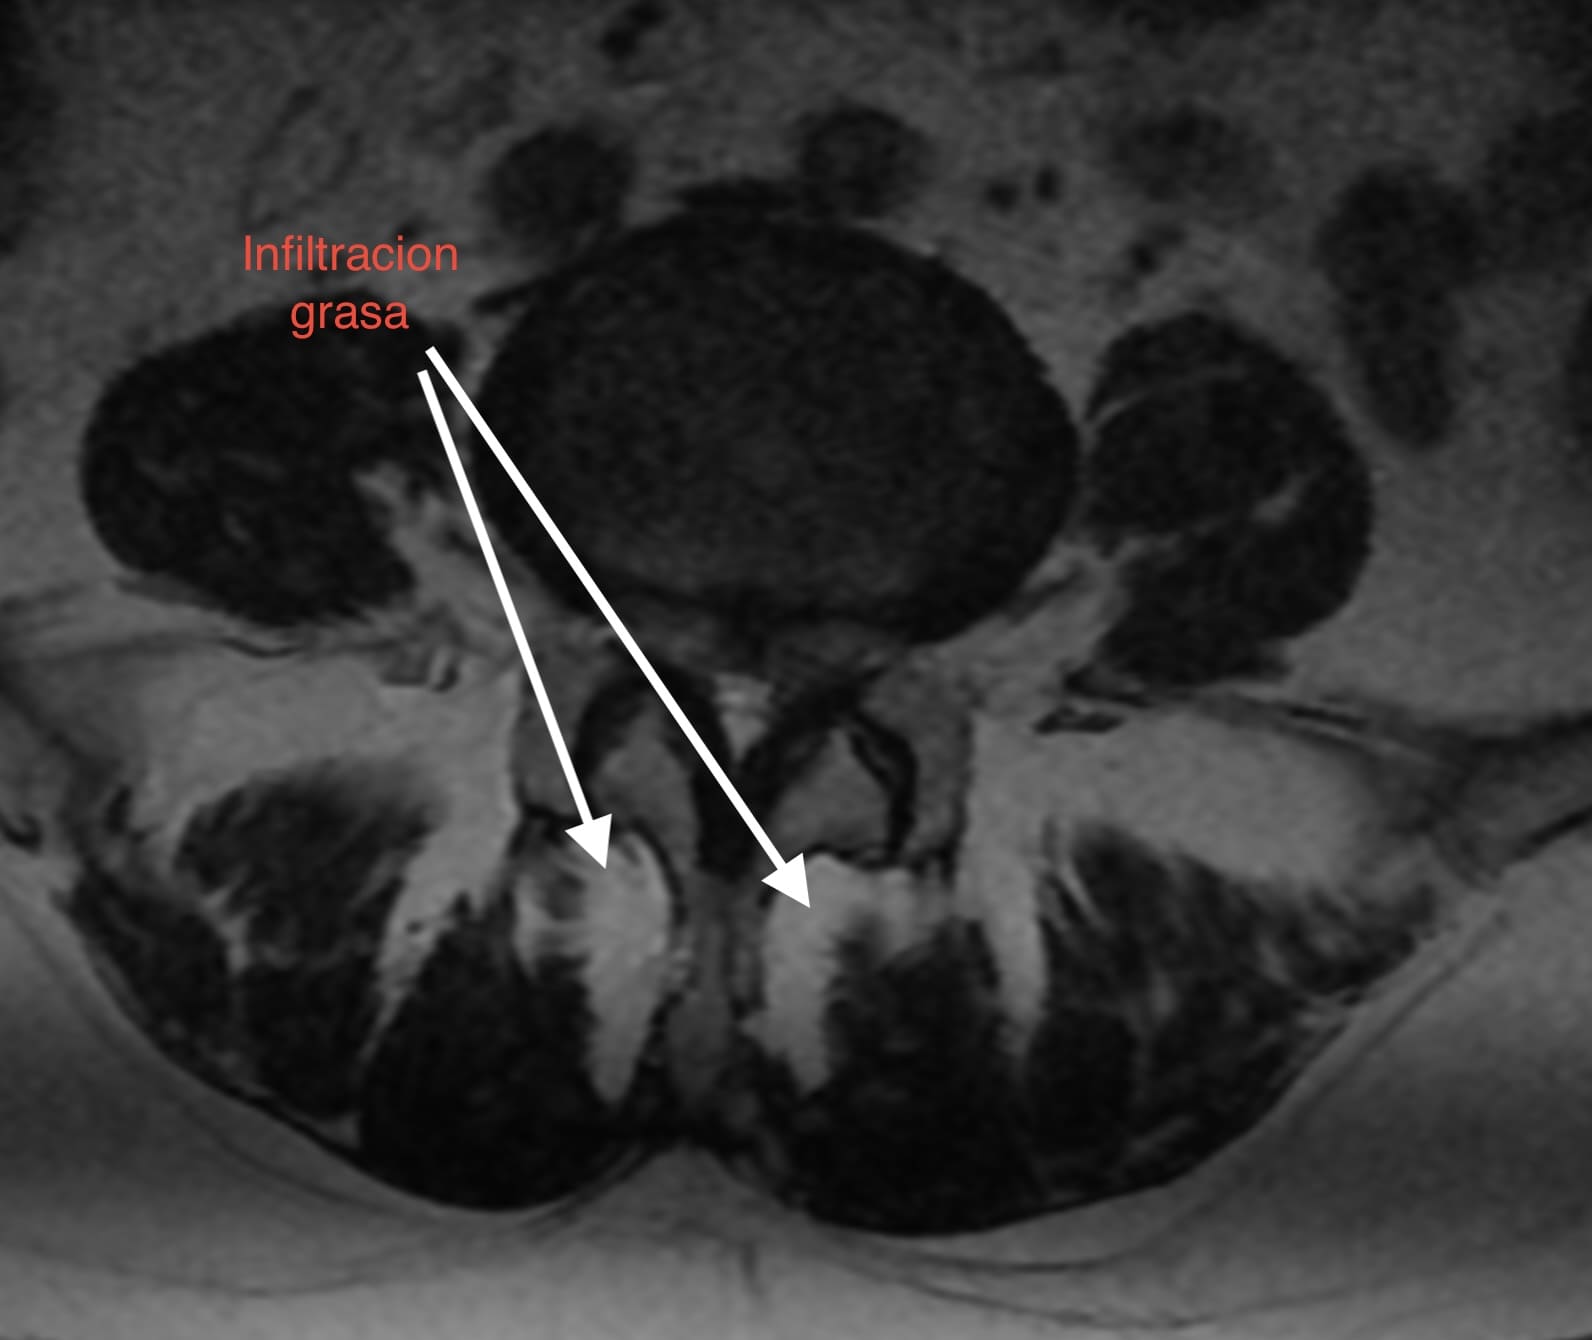

1. Pérdida del «Tirante» Dinámico: Los músculos multífidos actúan como estabilizadores segmentarios finos. En pacientes sarcopénicos, estos músculos son reemplazados por tejido adiposo no contráctil, perdiendo su capacidad de tensión.

• Calidad vs. Cantidad: La infiltración grasa (clasificación de Goutallier o medición de unidades Hounsfield en TAC) en el multífido es un factor de riesgo independiente para la reintervención. Músculos con alta infiltración grasa se correlacionan con peores resultados funcionales (ODI) y mayor tasa de complicaciones mecánicas como la cifosis de la unión proximal (PJK).

1. Screening Preoperatorio Rutinario: La RM lumbar debe utilizarse para evaluar la calidad muscular (corte axial en L3/L4), no solo la patología neural.